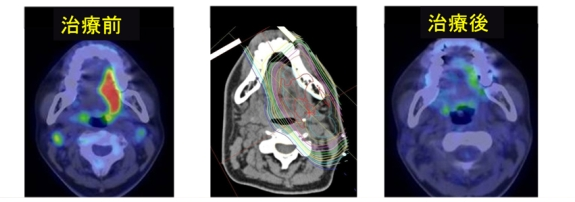

在X射線(xiàn)治療中,該院還積極進(jìn)行了近年來(lái)逐漸引起人們關(guān)注的容積調(diào)制電弧療法(VMAT),以及使用電子刀的立體定向放射療法用于頭頸部腫瘤的治療。

除了放射治療之外,還可以通過(guò)手術(shù)、化療等方法進(jìn)行癌癥治療,如可通過(guò)動(dòng)脈內(nèi)放化療治療包括舌癌和上頜竇癌在內(nèi)的口腔癌,這種結(jié)合了常規(guī)放療、動(dòng)脈內(nèi)灌注化療、IMRT或質(zhì)子治療的療法,可以在保證口腔內(nèi)器官功能的同時(shí),殺傷腫瘤,治療的效果可與手術(shù)媲美。該方法主要用于口腔癌,包括舌癌和上頜竇癌。特別是對(duì)于晚期舌癌,是一個(gè)很好的治療方法,可以有效保護(hù)舌頭。

▲動(dòng)脈內(nèi)放化療